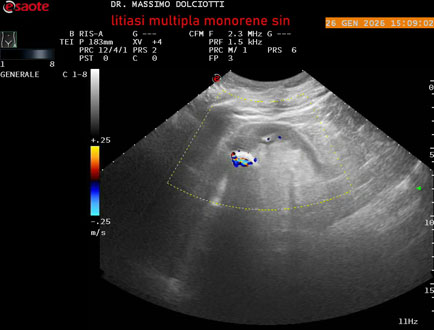

Data inserimento: 29/01/2026

Ecografia del: 26/01/2025

Strumento: Esaote MyLab Eight

Sonda: Conevx Multifrequenza 1-8 MHz

Età Paziente: M 78 anni

Motivazione dell'esame: follow up di litiasi al rene sinistro, in paziente sottoposto a nefrectomia destra.

Commento all'esame: le immagini ed il video documentano il rene sinistro in sede, di ecostruttura disomogenea per evidenza di multiple formazioni litiasiche al pielone superiore, delle dimensioni di 15,9 mm, al pielone medio di 17,5 mm e al pielone inferiore di 18,9 mm e morfovolumetria normale, con diametro bipolare di 115 (v.n. 90-120 mm) x 54 mm e parenchima renale dello spessore di 17 mm ( v.n. > 13 mm).

Conclusioni: litiasi multipla del monorene sinistro (multiple lithiasis of the left solitary kidney).